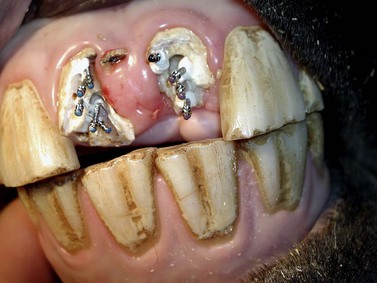

image

Fig. 22.3 Same horse as in Fig. 22.2. The fracture fragments and debris have been removed; the pulp canal of 202 has been drilled and curetted, and a paper point soaked in 0.8 % adrenaline solution is inserted into its pulp cavity for hemostasis. Filling with calcium hydroxide paste will now be performed.

In the horse, provided occlusal contact is avoided, additional restorative covers may not be necessary over the calcium hydroxide,1 especially if covered with a resin-containing calcium hydroxide preparation. Alternatively, the more occlusal endodontic calcium hydroxide cement can be removed, and a few millimeters of the root canal close to the masticatory surface can be sealed with glass ionomere21 or a resin-composite endodontic material. In show horses, incisors that are fractured at gingival level can be reconstructed using parapulpar pins and composite (Figs 22.422.7) to avoid protrusion of the tongue. The owners should be informed that the reconstructed crown has to be reduced at intervals to prevent occlusal contact with the opposite incisor; otherwise the artificial crown will inevitably break as human parapulpar pins and composite cannot withstand the forces of equine prehension. Owners should also be advised not to feed hay from nets, in order to reduce forces on the incisor restorations.